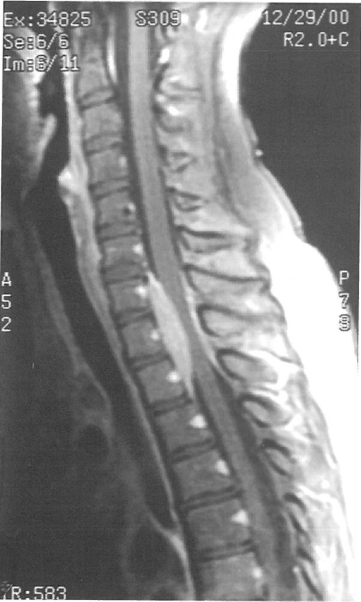

位于C7至T2节段的髓外硬膜内肿瘤包绕脊髓(图1和2)。

图1 MRI示C7到T2水平硬膜外肿瘤组织强化明显,并包绕脊髓。